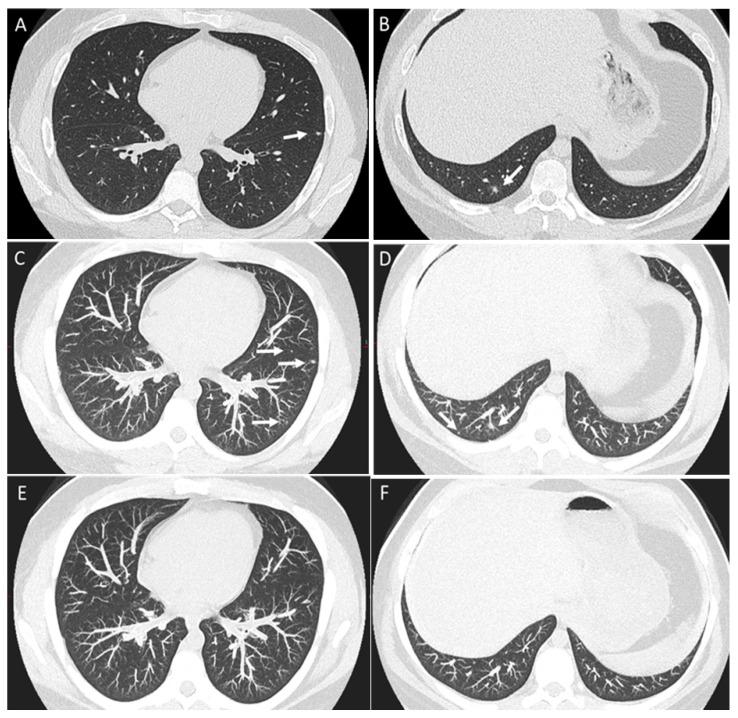

Osteosarcoma, a primary bone malignancy in children and adolescents, frequently metastasizes to the lungs, contributing significantly to morbidity and mortality. At diagnosis, 15-20% of patients present with detectable lung metastases. Chest computed tomography (CT) is vital for the early detection and monitoring of these metastases. Lung involvement typically presents as multiple nodules of varying sizes and can include atypical features such as cavitation, cystic lesions, ground-glass halos, intravascular tumor thrombi, and endobronchial disease. Pleural metastasis often occurs alongside pulmonary disease, and complications like spontaneous pneumothorax may arise. Additional findings may include thoracic lymphadenopathy, cardiac tumor thrombus, and chest wall deposits. Familiarity with these imaging patterns is essential for radiologists to ensure timely diagnosis and effective management. This review highlights the critical role of chest CT in detecting and characterizing osteosarcoma metastasis.

骨肉瘤是儿童和青少年常见的原发性骨恶性肿瘤,常转移至肺部,对发病率和死亡率有显著影响。在诊断时,15%至20%的患者出现可检测到的肺转移。胸部计算机断层扫描(CT)对于这些转移灶的早期检测和监测至关重要。肺部受累通常表现为大小不一的多个结节,可包括一些非典型特征,如空洞形成、囊性病变、磨玻璃晕、血管内肿瘤血栓和支气管内病变。胸膜转移常与肺部疾病同时发生,可能出现自发性气胸等并发症。其他表现可能包括胸内淋巴结肿大、心脏肿瘤血栓和胸壁转移灶。放射科医生熟悉这些影像学表现对于确保及时诊断和有效治疗至关重要。本综述强调了胸部CT在检测和鉴别骨肉瘤转移方面的关键作用。